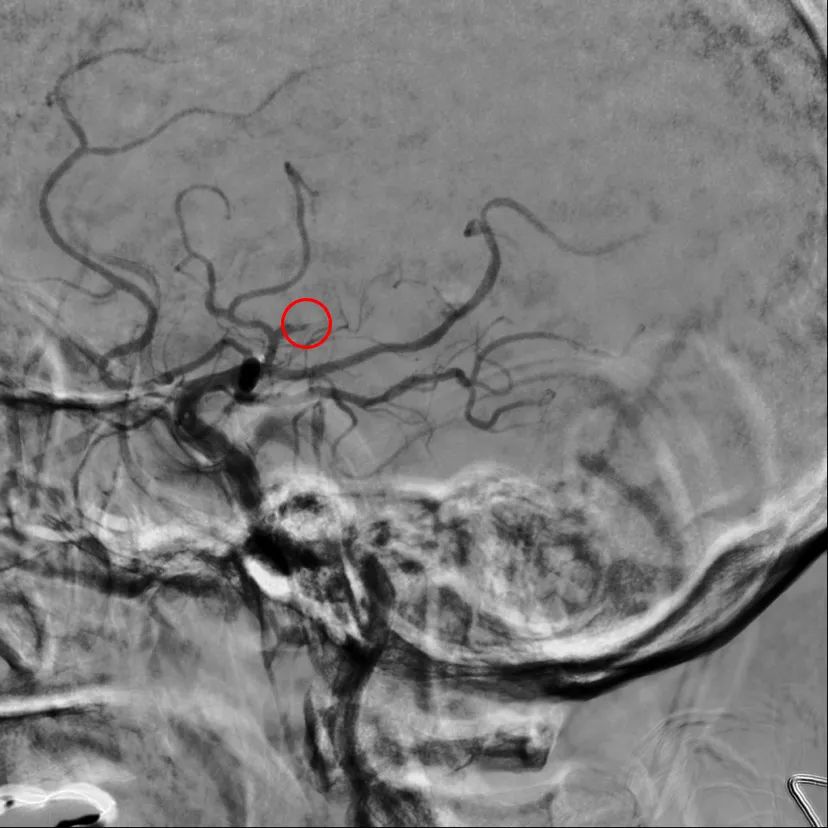

16 时 55 分,梅爷爷被送入介入室,在脑卒中绿色通道救治团队快速且充分的准备后,17 时 10 分,神经疾病科史树贵教授、翟红教授、卢龙医师紧急为梅爷爷行脑血管造影+脑动脉支架取栓术。

17 时 56 分,堵在梅爷爷右侧大脑动脉的血栓被取出,手术顺利完成。

上图为取栓前,中图为取栓后,下图为取出血栓